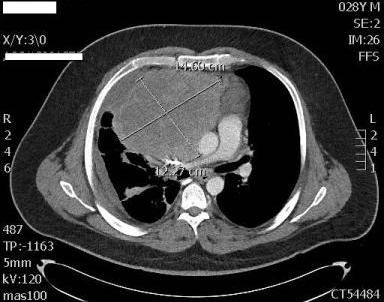

Figure 1. Transverse thoracic CT (click to enlarge)

In the ED, the patient was in acute respiratory distress and coughing violently. Initial examination revealed diminished breath sounds in the right lung field. CT scans of his chest, abdomen, and pelvis revealed a 12.9-cm right-sided anterior mediastinal mass; a large right pleural effusion; mediastinal lymphadenopathy; a small pericardial effusion; and prominent lymph nodes in the celiac, mesentery, and portocaval regions with a hypodensity in the hepatic lobe. The mass was compressing the right atrium, superior vena cava, and right lung (Figures 1 and 2). The patient was admitted to medicine.